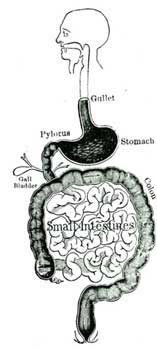

9. The Gullet.—At the back part of the throat begins a narrow tube, which passes down to the stomach. This tube is about nine inches long. It is called the gullet, food-pipe, or œsophagus (e-soph´-a-gus).

10. The Stomach.—At the lower end of the œsophagus the digestive tube becomes enlarged, and has a shape somewhat like a pear. This is the stomach. In a full-grown person the stomach is sufficiently large to hold about three pints. At each end of the stomach is a narrow opening so arranged that it can be opened or tightly closed, as may be necessary. The upper opening allows the food to pass into the stomach, the lower one allows it to pass out into the intestines. This opening is called the pylorus (py-lo´-rus), or gate-keeper, because it closes so as to keep the food in the stomach until it is ready to pass out.

11. In the membrane which lines the stomach there are many little pocket-like glands, [Pg 32]in which a fluid called the gastric juice is formed. This fluid is one of the most important of all the fluids formed in the digestive canal.

12. The Intestine(in-tes´-tine).—At the lower end of the stomach the digestive canal becomes narrow again. This narrow portion, called the intestine, is about twenty-five feet long in a grown person. The last few feet of the intestine is larger than the rest, and is called the colon. This long tube is coiled up and snugly packed away in the cavity of the abdomen. In the membrane lining the intestines are to be found little glands, which make a fluid called intestinal juice.

13. The Liver.—Close up under the ribs, on the right side of the body, is a large chocolate-colored organ, called the liver. The liver is about half as large as the head, and is shaped so as to fit snugly into its corner of the abdomen. The chief business of the liver is to make a fluid called bile, which is very necessary for the digestion of our food.

14. The bile is a bitter fluid of a golden-brown color. It is carried to the intestine by means of a little tube or duct, which enters the small in[Pg 33]testine a few inches below the stomach. When the bile is made faster than it is needed for immediate use, it is stored up in a little pear-shaped sac called the gall-bladder, which hangs from the under side of the liver.

15. The liver is a very wonderful organ, and does many useful things besides making bile. It aids in various ways in digesting the food, and helps to keep the blood pure by removing from it harmful substances which are formed within the body.

16. The Pancreas(pan´-cre-as).—The pancreas is another large and very important gland which is found close to the stomach, lying just behind it in the abdominal cavity. The pancreas forms a fluid called the pancreatic juice, which enters the small intestine at nearly the same place as the bile.

17. The Spleen.—Close to the pancreas, at the left side of the body, is a dark, roundish organ about the size of the fist, called the spleen. It is not known that the spleen has much to do in the work of digestion, but it is so closely connected with the digestive organs that we need to know about it.

18. Please note that there are five important organs of digestion. The mouth, the stomach, the intestines, the pancreas, and the liver.

[Pg 34]19. Also observe that there are five digestive fluids, saliva, gastric juice, bile, pancreatic juice, and intestinal juice.